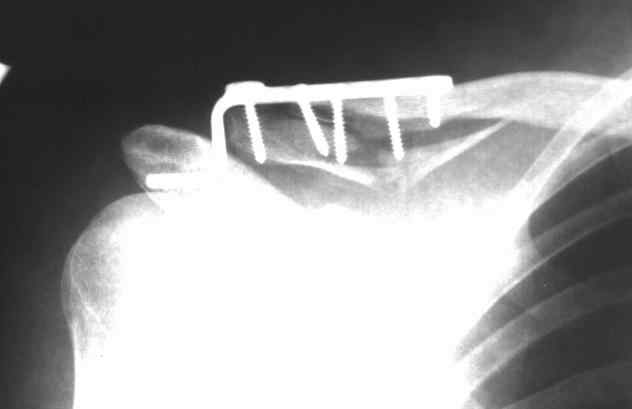

Пациент,32 года, травма - падение с высоты на правое плечо. Прооперирован 20.05.08.... Ad oculus, при ревизии перелома, многооскольчатый перелом, акромиально-ключичное сочленение сохранено. Коллеги, прошу высказать ваше мнение по поводу данного случая: Выбор метода? качество остеосинтеза? ваш вариант лечения? Возможные осложнения? Спасибо!

http://В данном случае применениtй крючковидной пластины вполне оправдано. К сожадению выбран неправилиный размер фиксатора. Удлиненный вариат пластины решил бы все проблемы.

К сожалению спектр таких пластинок представляемый фирмой "Деост"(не реклама) в нашем регионе, заканчивается на 6 дырках. Да и крючок стал одного размера, а раньше был вариабельный.